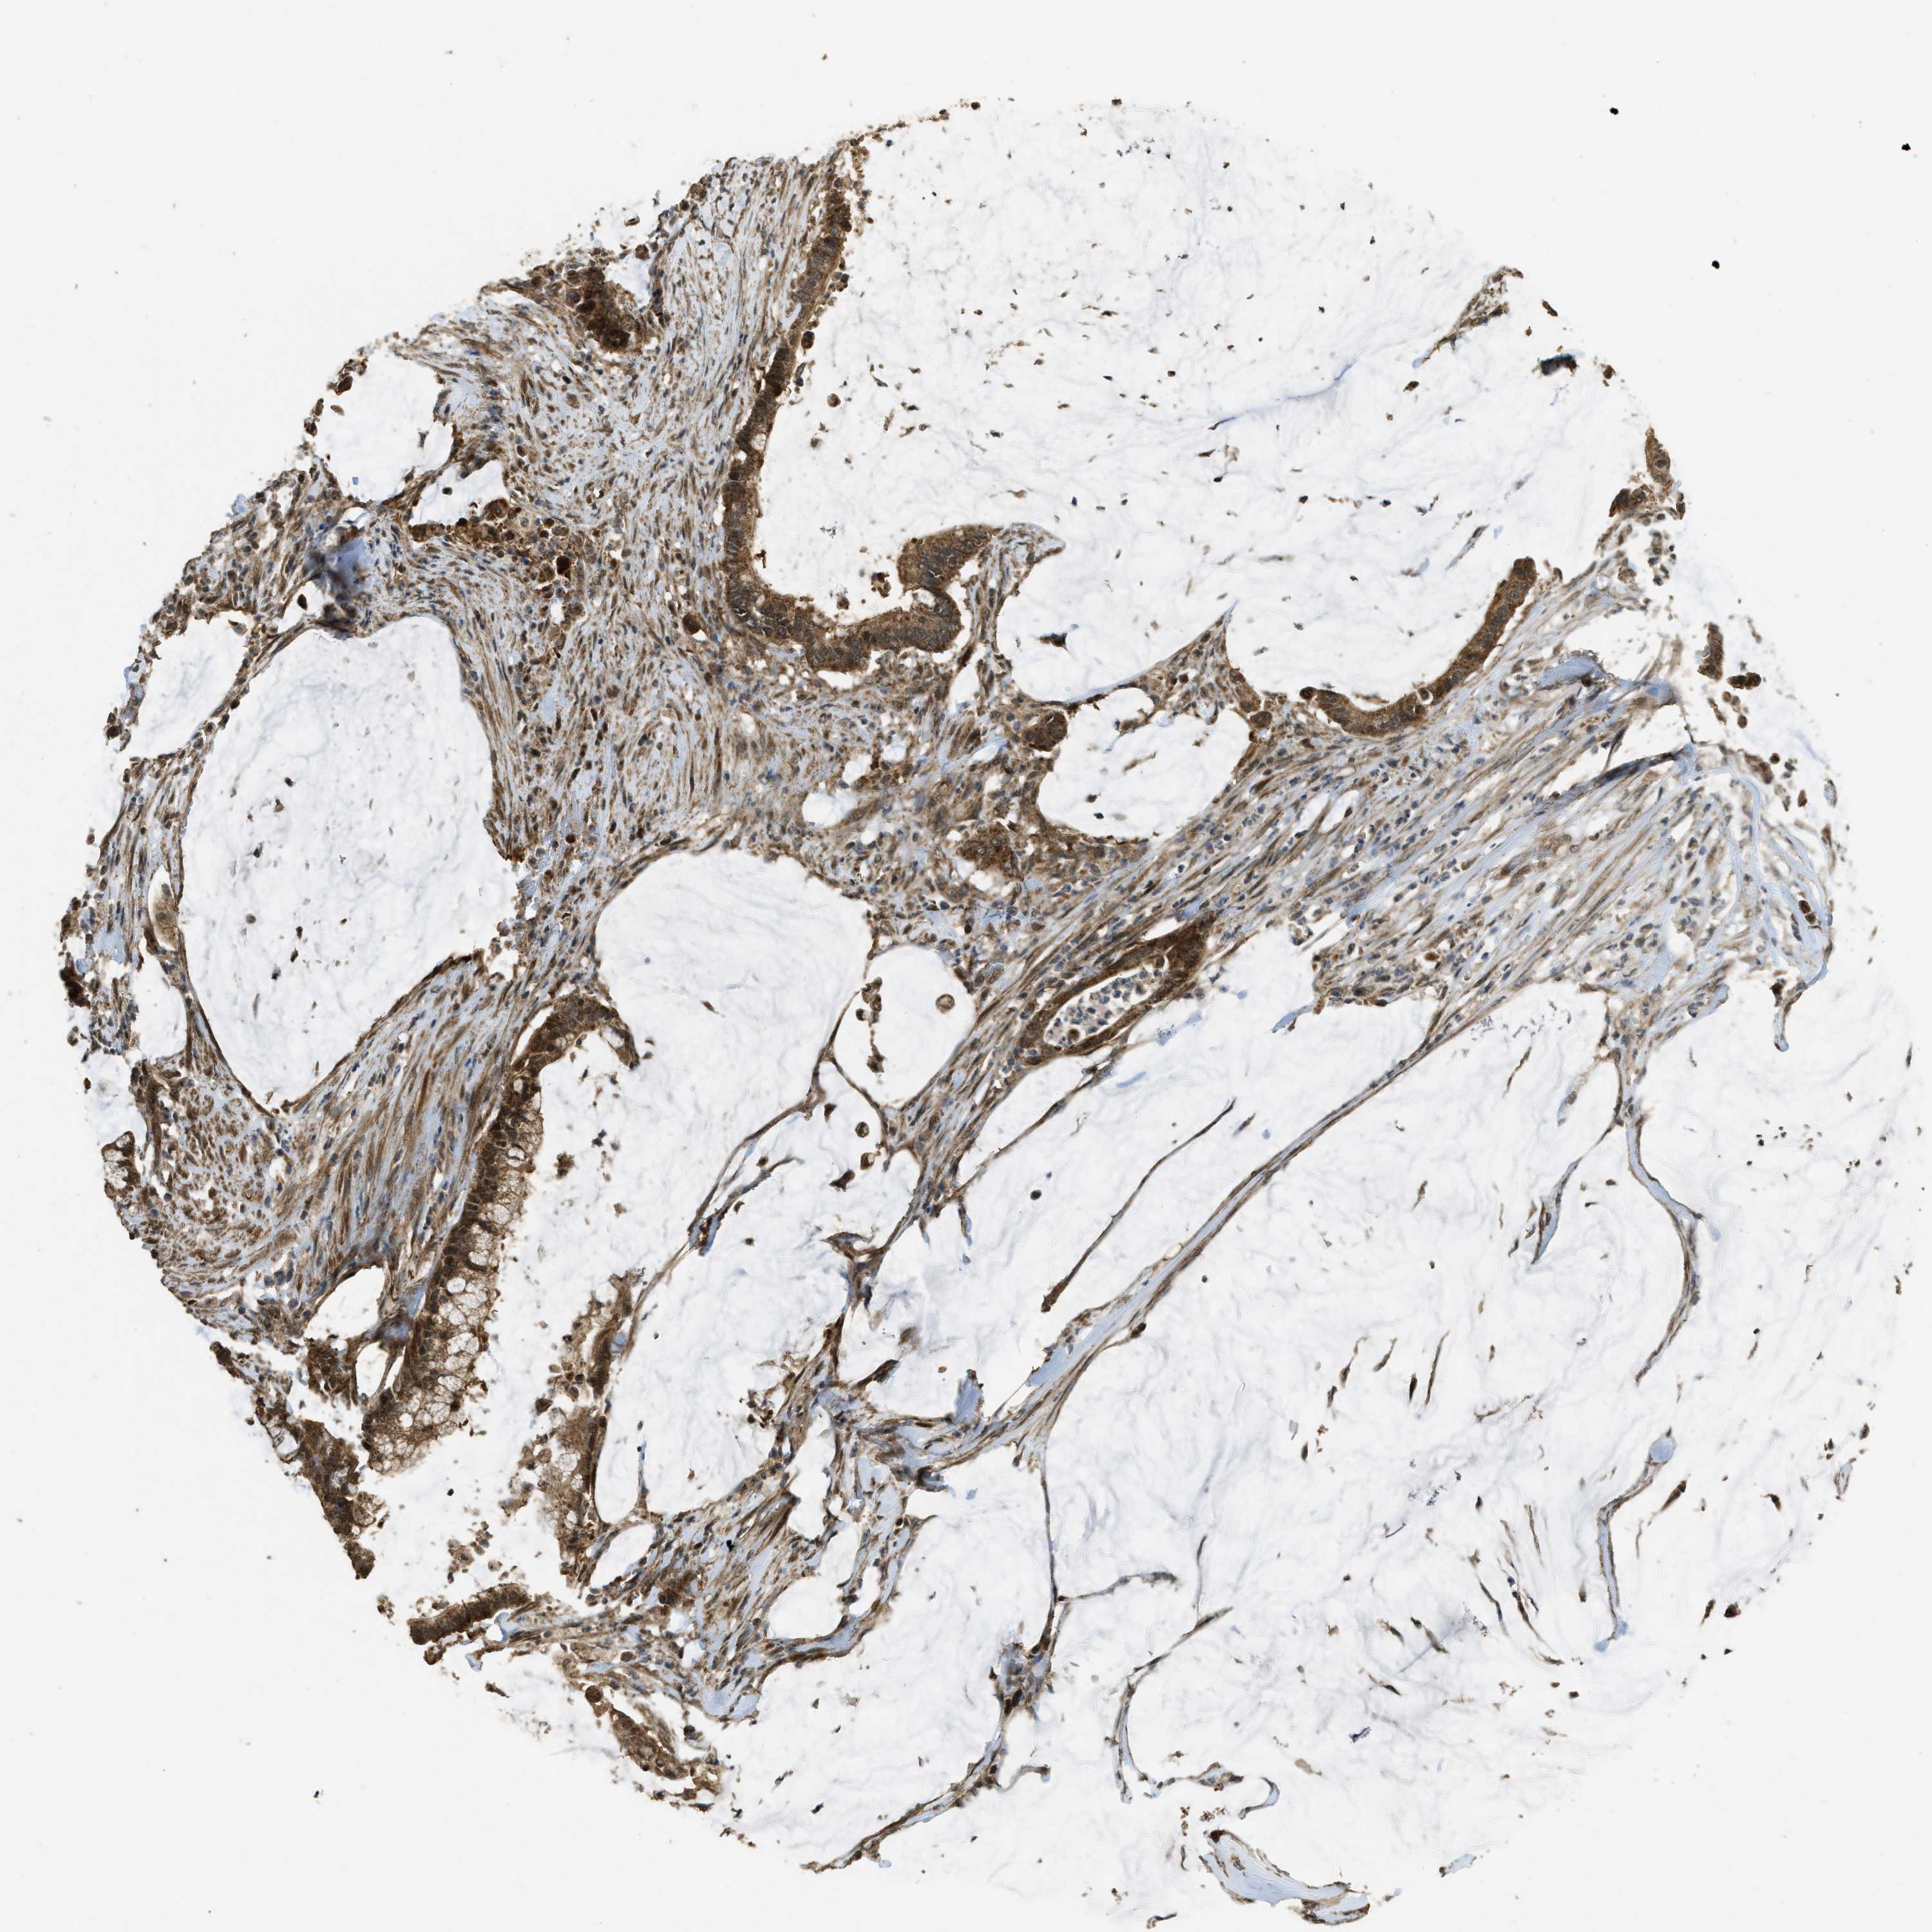

PANCREATIC CANCER - Protein expressioni

A mouse-over function shows sample information and annotation data. Click on an image to view it in a full screen mode. Samples can be filtered based on level of antibody staining by selecting one or several of the following categories: high, medium, low and not detected. The assay and annotation is described here.

Note that samples used for immunohistochemistry by the Human Protein Atlas do not correspond to samples in the TCGA dataset.

Antibody stainingi

Antibody staining in the annotated cell types in the current human tissue is reported as not detected, low, medium, or high, based on conventional immunohistochemistry profiling in selected tissues. This score is based on the combination of the staining intensity and fraction of stained cells.

Each image is clickable and will lead to virtual microscopy that enables deeper exploration of all samples and also displays staining intensity scores, fraction scores and subcellular localization as well as patient and tissue information for each sample.

Antibody HPA051322

Antibody CAB017111

Staining

High

Medium

Low

Not detected

Intensity

Strong

Moderate

Weak

Negative

Quantity

>75%

75%-25%

<25%

None

Location

Nuclear

Cytoplasmic/membranous

Cytoplasmic/membranous,nuclear

Adenocarcinoma, NOS